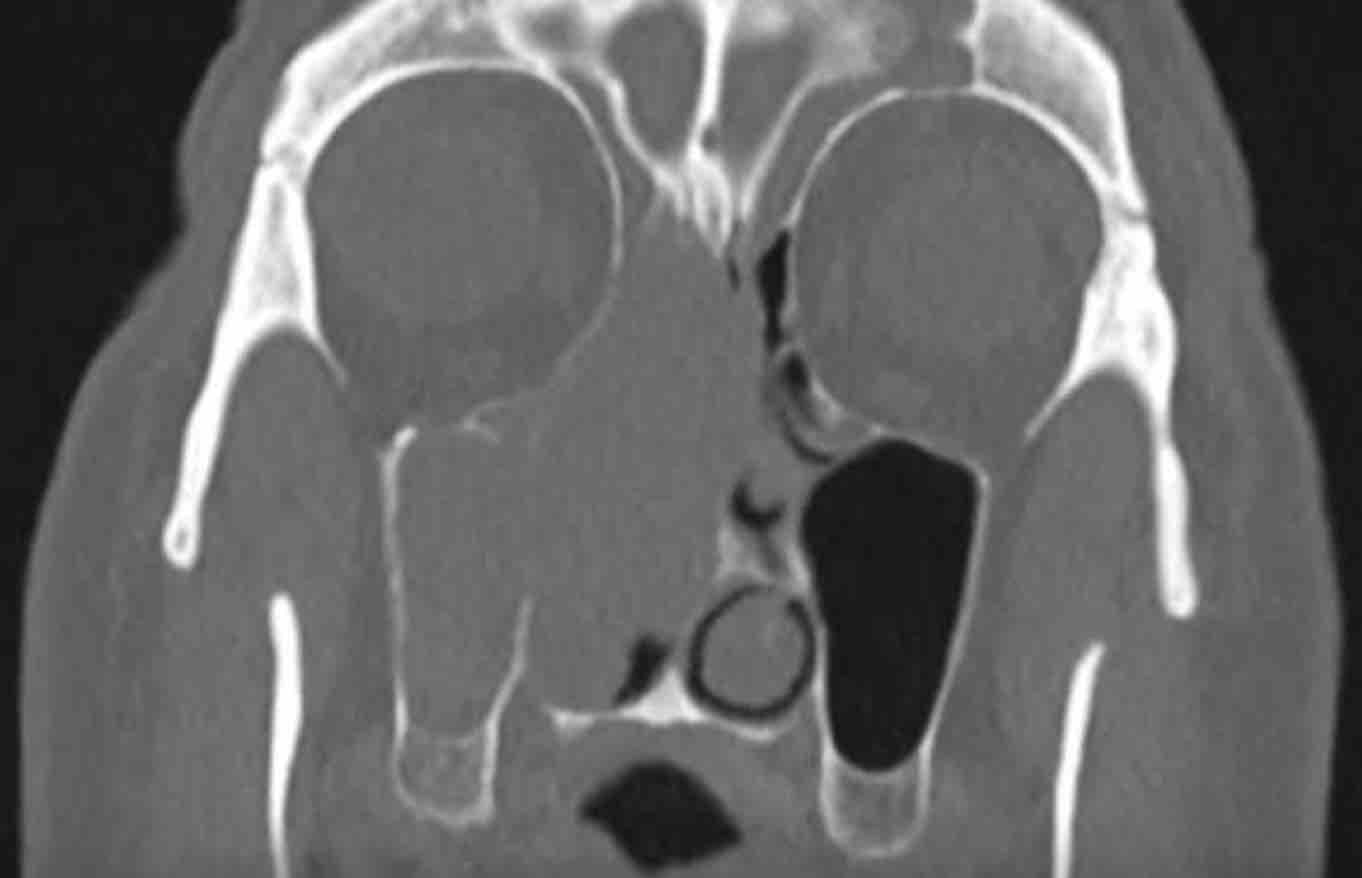

Bệnh nhân này có nang nhầy ở xoang hàm trái với giãn rộng nhẹ (mũi tên trắng).

Bên phải có một khối không có giãn rộng (đầu mũi tên vàng) và vẫn còn một ít khí trong xoang hàm.

Đây là nang ứ dịch.

Bệnh nhân này cũng có nang nhầy ở xoang hàm trái.

Bên phải có tình trạng lấp đầy hoàn toàn xoang hàm, nhưng không có giãn rộng.

Do đó, trường hợp này không đáp ứng tiêu chuẩn để chẩn đoán nang nhầy.